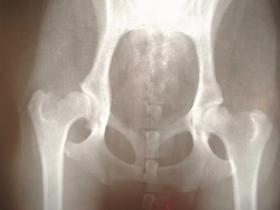

腸脛靭帯炎は大腿筋膜張筋と大殿筋がポイント

腸脛靭帯は、大腿筋膜張筋と大殿筋の合同の腱になります。腸脛靭帯炎は、腸脛靭帯が張りすぎてしまうことで、大腿骨とぶつかり、炎症と痛みを起こします。

腸脛靭帯を張らせる原因は、大腿筋膜張筋、大殿筋の緊張です。緊張を緩めることで、腸脛靭帯を緩めます。カラダの軸がずれていることにより、腸脛靭帯が張りますので、カラダの軸の調整も一緒におこなうことで再発を防ぎます。